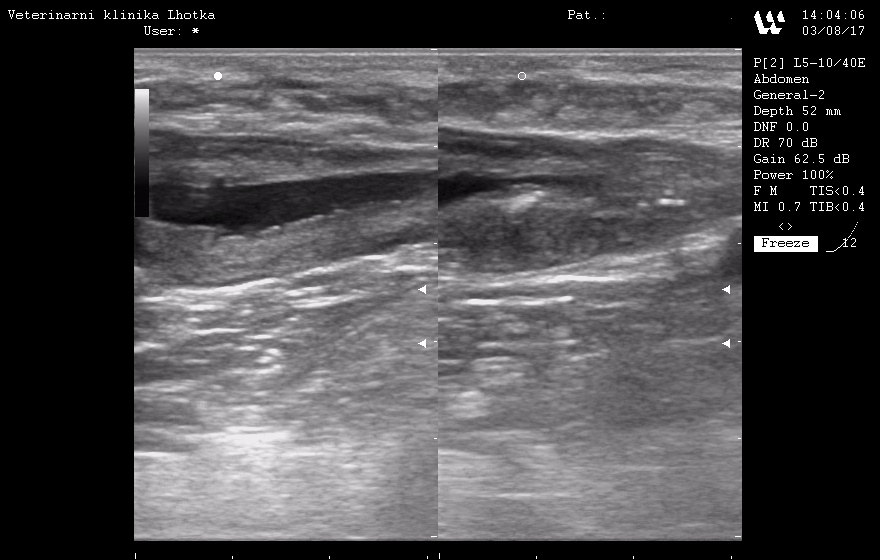

Naštěstí v případě Agáthy tato opatření fungují. Moč má potřebné charakteristiky – UG 1025 až 1030, pH 6 až 6,5 a v močovém sedimentu opakovaně nenacházíme žádné krystaly ani příznaky UTI. Stejně tak při sonografických kontrolách se v lumen močového měchýře netvoří žádné urolity nebo močový písek.

SONO MM po operaci.jpg